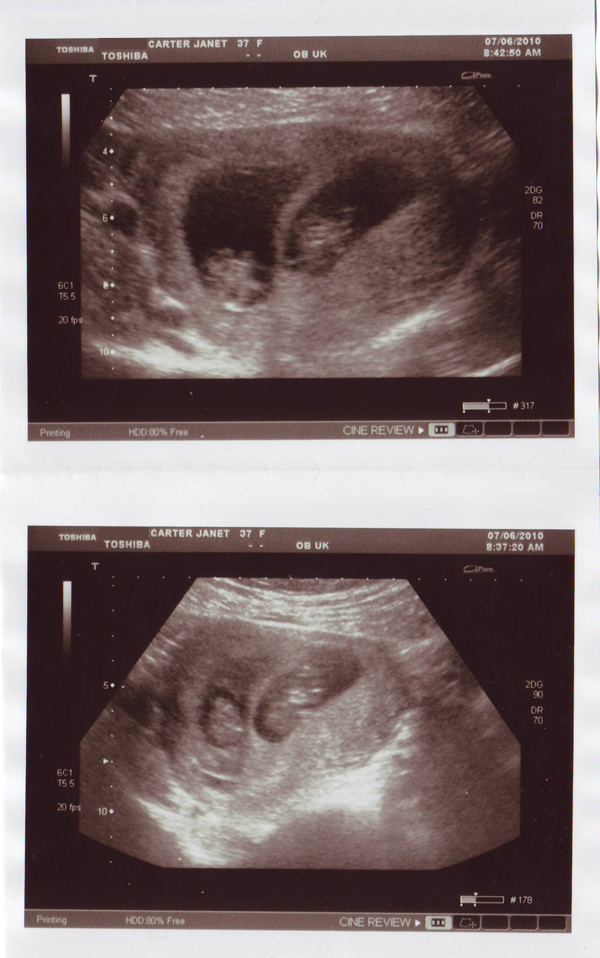

To twins!

Twins2_web

How very, very exciting! I'm hoping there's at least one little girl in there so that I can make cute wee dresses. These scans were taken a few weeks back when Janet was 11 weeks pregnant and now she's 16 weeks and showing a baby bump. They are due end of December, initally they thought on my birthday. However being twins they won't let Janet go any longer than 38 weeks so they will be here before Christmas. When Janet and Richard told my boys they were expecting Matthew was so happy that he cried, bless him. He then asked if he could take the scans into school for Show and Tell (I copied the original scans) and I told him to make sure everyone knew it was his Auntie who was pregnant and not Mummy!